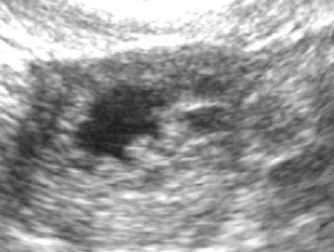

Сегодня на 28 ДЦ пошла на УЗИ (в другое место), т.к. 2 дня очень обильные выделения ЯБ. В результате эндометрий 13мм, в ЛЯ формируется желтое тело 20х22мм, небольшое кол-во жидкости есть. Узистка сказала, что прямо сейчас происходит овуляция, ЖТ только начало формироваться.

Это как понимать? За 4 дня фоллик с 11мм так вырос и совулировал? посмотрите фотки, плиз, кто понимает, я в этом полный профан. И как думаете в постель уже поздно ложиться?

А подскажите кто разбирается ЖТ на каком из этих фото?

на снимках не видно жт

оно обычно серого цвета с неровными краями.

на первом фото у вас 100% фолликулы.

на 2 фото больше похож на фолликул, так как края ровные, но внутри серое включение, может формируется жт.

на 3 фото матка.

вот так выглядит желтое тело